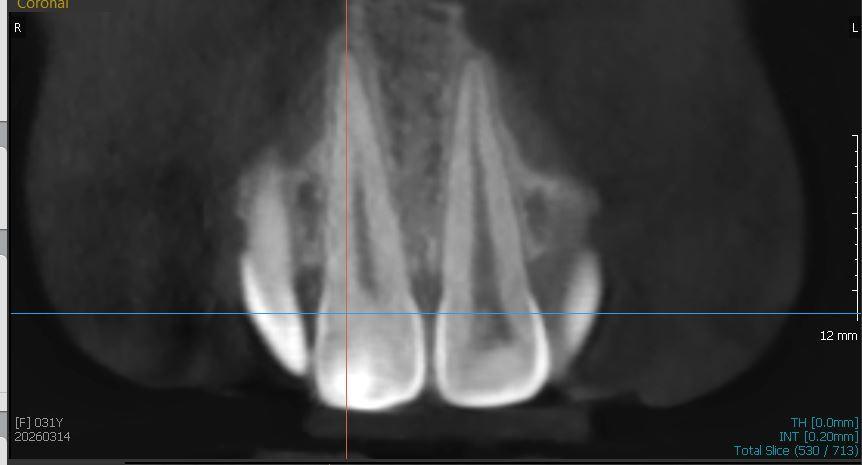

Вчера сделала КТ.

Юрий Жигурт, Подскажите, пожалуйста, есть ли кариес на 11 зубе (сторона контактная с 12 зубом)? Или его признаки. Если да, то насколько глубоко? Если возможно покажите, пожалуйста, стрелочкой где это наблюдается. Спасибо!

anastasiiia, есть основания предполагать:

Я была у нескольких врачей, один сказал - трогать не стоит, возможно не будет развиваться или крайне медленно будет развиваться, второй сказал, что вообще ничего нет в дентине. Но у меня сомнения(